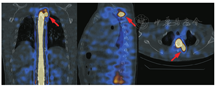

患者男,36岁,无明显诱因突发间断性头晕、头痛3个月余,表现为视物旋转,反复发作,多于活动时出现,每次持续数分钟,严重时伴恶心、呕吐,休息后可好转。否认高血压、冠状动脉粥样硬化性心脏病、糖尿病及外伤史。体格检查:四肢肌张力正常,双侧腱反射对称,未见明显感觉障碍。实验室检查(括号内为正常参考值范围):血常规WBC计数[18.59(3.50~9.50)×109/L]及中性粒细胞百分比稍增高[80%(50%~70%)];丙氨酸氨基转移酶升高[96.0(0.0~50.0) U/L]。颅脑MRI及弥散加权成像(diffusion weight imaging, DWI)未见明显异常。腰椎穿刺后测得脑脊液压力为0.58(0.78~1.76)kPa,脑脊液常规检查结果示细胞总数为1 003.0(0.0~8.0)×106/L,WBC计数为3.0(0.0~5.0)×106/L,蛋白质为0.9(0.2~0.4) g/L。结合病史及上述检查结果,倾向于诊断颅内感染。按照病毒性脑炎治疗后,患者仍间断头痛且剧烈,坐起时明显,最终临床考虑自发性低颅压综合征(spontaneous intracranial hypotension syndrome, SIHS)可能性大,对患者行CT及MRI查找脑脊液漏口。胸部CT(图1)示椎管内未见明显异常,胸、腰椎增强MRI(图2)示椎管内异常强化影,未见明确漏点,首先考虑SIHS。由于上述检查未能发现明确漏点,遂行核素脑池显像,检查前患者签署知情同意书。仪器为美国GE Discovery-670Pro SPECT/CT仪,显像剂99Tcm-二乙撑三胺五乙酸(diethylene triamine pentoacetic acid, DTPA)注射液由本科室自制(注射用亚锡喷替酸由北京师宏药物研制中心提供)。腰椎穿刺成功后,接上装有显像剂的注射器,取缓慢流出的脑脊液稀释至2.5 ml,再缓慢将110 MBq(0.8 ml)显像剂推注到蛛网膜下腔,然后放入针芯,拔针,盖敷料,患者去枕平卧休息30 min。于注入显像剂后0.5、1.5、2及3 h行局部(颈胸段)平面显像,3.5 h行局部SPECT/CT显像。0.5 h平面显像示从腰段至枕大池,脊髓蛛网膜下腔显影,放射性分布均匀,未见明显异常放射性分布浓聚影(图3A);1.5 h及2 h显像示上后纵隔、左侧椎旁见局灶性放射性浓聚影,似与椎管相连(图3B,图3C);3 h显像示上后纵隔、左侧椎旁放射性影像较前稍增浓(图3D);3.5 h SPECT/CT显像示胸2椎水平左侧附件区、椎管旁见局限性放射性浓聚影且与椎管影像相连(图4)。根据核素脑池显像影像表现,临床行手术探查,术中在显微镜下可见胸2神经根处蛛网膜撕裂并漏出清亮脑脊液,仔细分离出漏口,2次缝扎并用耳脑胶封闭漏口处。术后1个月及1年随访2次,患者已无头痛、头晕等症状,临床治愈。

核素脑池显像是核医学经典显像方法,诊断脑脊液漏并不困难,但由于解剖定位功能弱,其临床应用受限。随着核医学设备的发展,SPECT/CT在脑脊液漏诊断及定位上优势显著。本例患者注射显像剂后0.5 h显像图上虽没有见到放射性异常浓聚影,但在注射后1.5 h及2 h后位图像上均可观察到椎管左旁局灶性放射性异常浓聚影,虽然显影较淡,但结合病史需考虑到此处脑脊液漏的可能,因此需进行多时相延迟采集;3 h后位图像上该处放射性异常浓聚影较2 h显影更清晰,提高了诊断信心;3.5 h SPECT/CT显像将漏点精准定位于胸2椎椎管左旁,术后证实该处神经根蛛网膜撕裂。